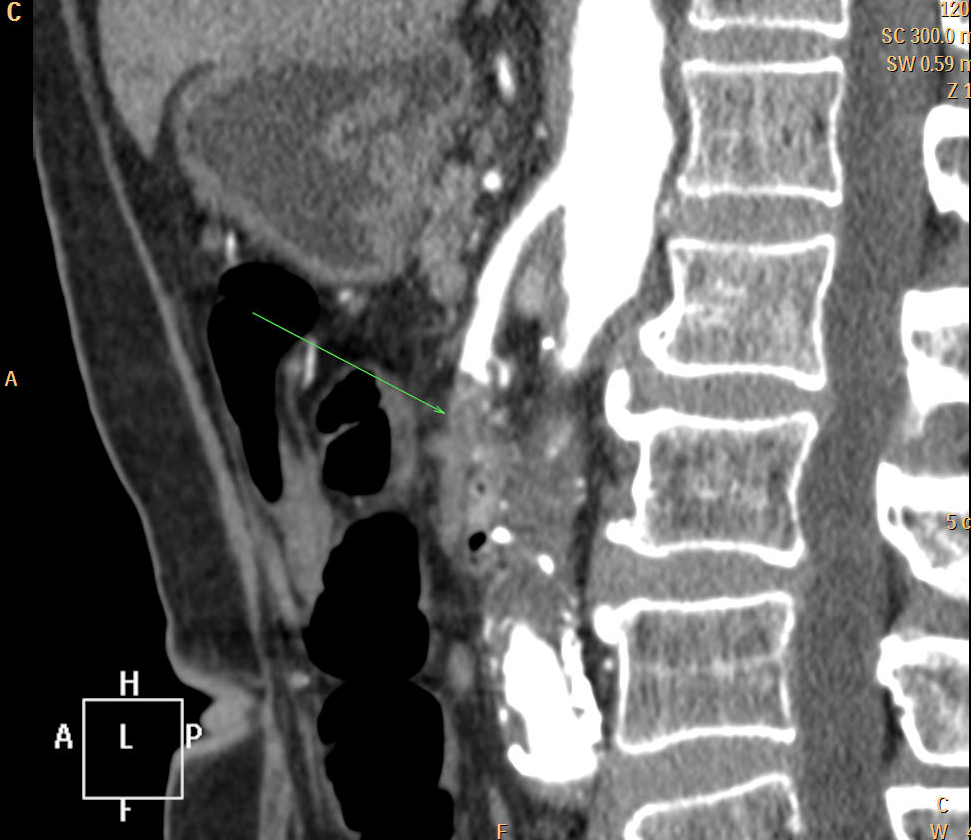

• In acute neck pain, jaw-lock, difficulty with breathing can be caused by a complicated dental or pharyngeal infection. The role of imaging to detect the cause of dyspnea, and potential mediastinal or spinal spread of the inflammation. US of the neck is flexible and fast but only can penetrate superficial tissues, and has to be used in combination with other modalities. Its primarily used to detect fluid collections, solid nodules, or to guide image guided interventions such as aspiration or abscess drainage. In the infrahyoid region CT and MRI can be used with similar efficiency as both have certain disadvantages. CT is faster, and less sensitive for motion and metallic artefacts. (Meanwhile, in the suprahyoid region MRI provides better soft tissue contrast.)